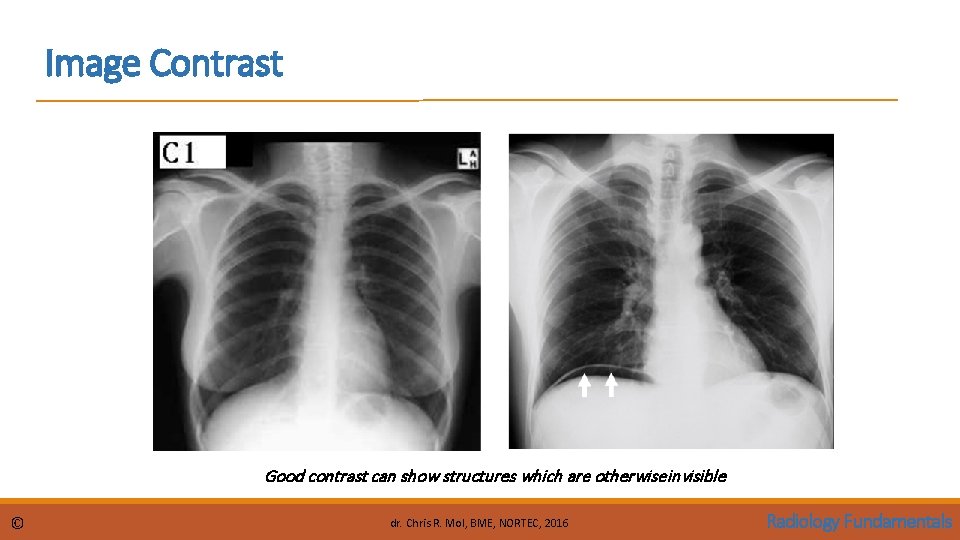

Image Contrast Good contrast can show structures which are otherwise invisible © dr. Chris R. Mol, BME, NORTEC, 2016 Radiology Fundamentals